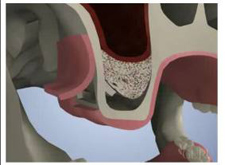

術前CT 1

第二小臼歯部

サイナスリフトと同時にインプラントを埋入

術前CT 2

第一大臼歯部

サイナスリフトによりインプラントの埋入が可能